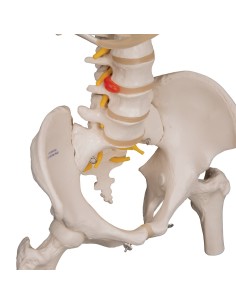

Colonne lombaire 3B Scientifique avec hernie discale dorsolatérale A76/5